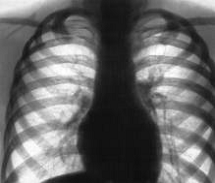

Приложение

2.

Заражённые легкие.

Здоровые легкие.

3

Заражённые лёгкие.